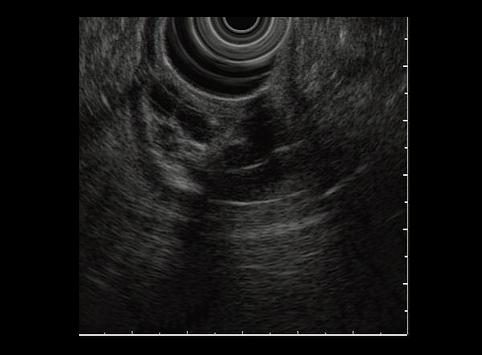

疾病(病理主体)的分类肿瘤样病变/异位粘膜

部位(按器官分)胃(部位)/前庭

检查方法超声波

肿瘤最大直径30~34